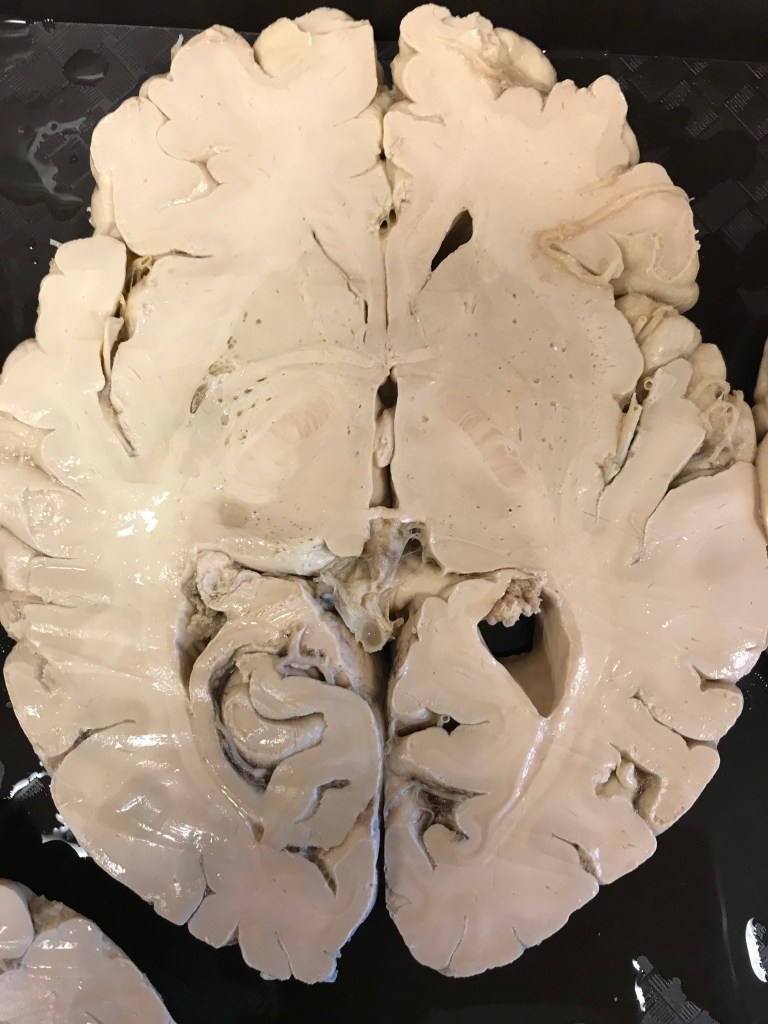

An axial cut showing the dark cell bodies of the basal ganglia